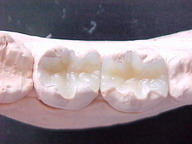

Fase laboratorial ONLAY ARTGLASS